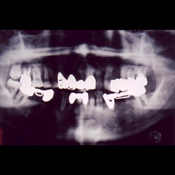

レントゲン写真よりトレースされた図面、いわば歯科医の設計図です。これをもとにインプラント体の埋入本数や位置、サイズを決めていきます。

インプラント、人工歯根、上部構造を口の中に装着した時のレントゲン写真です。